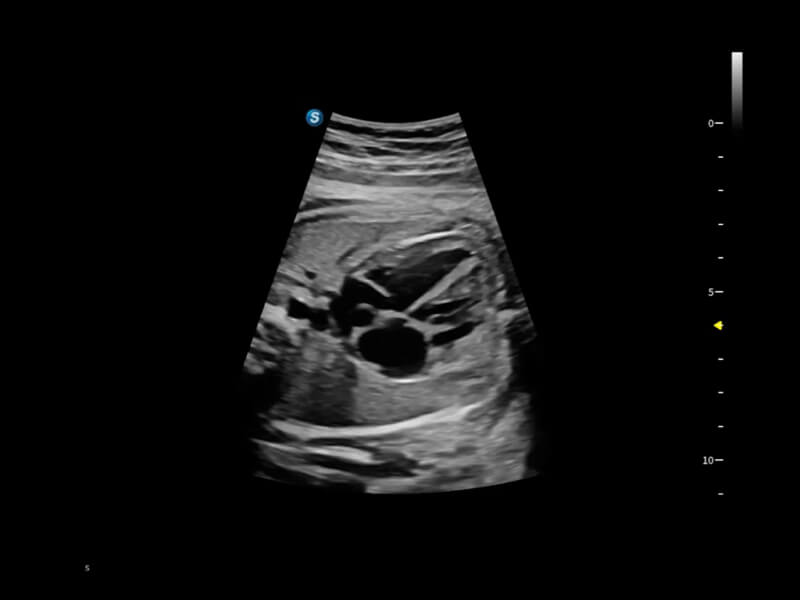

作为开立医疗全新打造的超高端旗舰超声产品,从探头抬起唤醒开启扫查到多维探头发射接收,通过先进的场成像发射、自适应聚合重建等技术,基于RF Data原始射频数据在图像生成、高端功能等方面实现突破,为妇产科、儿科提供全方位临床解决方案。

梦溪®P80以“关爱女性”为基石,提供全方位的解决方案,量身定制以满足女性的健康需求,涵盖妇科、生殖健康检查、产前筛查及产后康复等领域。

丰富的血流动力学检测技术,可在不同医疗场景中高效捕捉血流信号,助力临床诊疗。